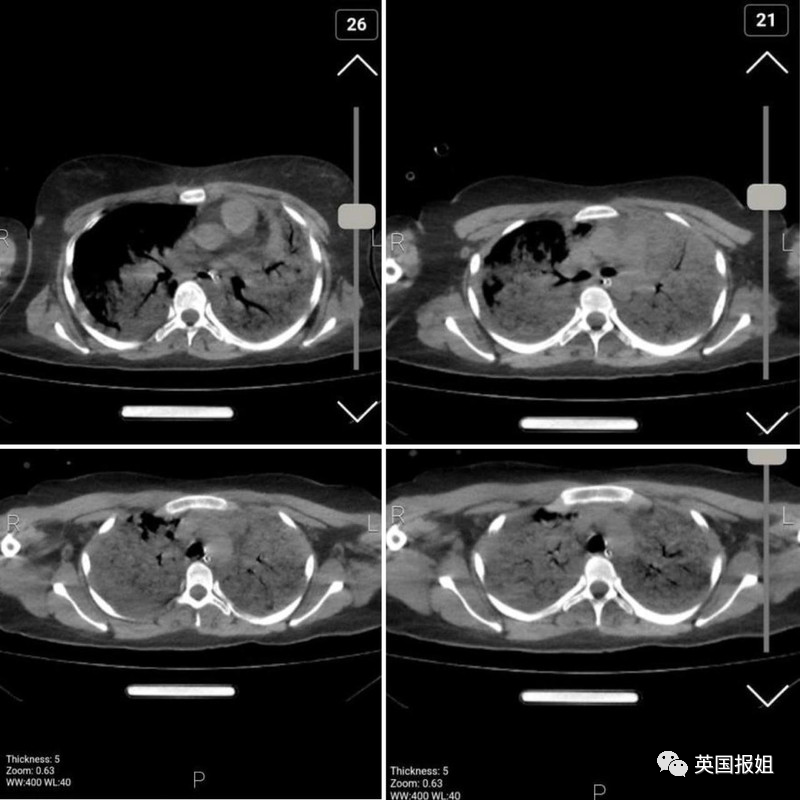

在此之后,数十张被公布的CT扫描结果更是让人们的愤怒达到了顶峰。

9月19日,数张CT扫描影像被匿名发送给了伊朗国际组织和媒体。

影像显示,她头部右侧的颅骨骨折、出血、脑水肿;胸部有双侧弥漫性肺泡出血,与脑外伤引起的急性呼吸窘迫综合征症状相符。